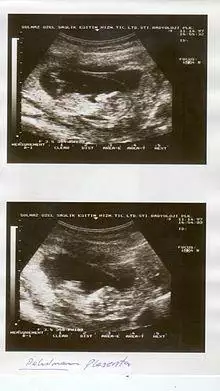

Ultrasound showing placental abruption.

Placental abruption is suspected when a pregnant mother has sudden localized abdominal pain with or without bleeding. The fundus may be monitored because a rising fundus can indicate bleeding. An ultrasound may be used to rule out placenta praevia but is not diagnostic for abruption.[8] The diagnosis is one of exclusion, meaning other possible sources of vaginal bleeding or abdominal pain have to be ruled out in order to diagnose placental abruption.[5] Of note, use of magnetic resonance imaging has been found to be highly sensitive in depicting placental abruption, and may be considered if no ultrasound evidence of placental abruption is present, especially if the diagnosis of placental abruption would change management.[16]